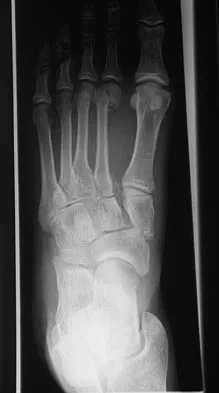

A 21-year-old football player who sustained a direct blow to the posterior hindfoot while making a cut is unable to bear weight on the injured foot. Examination reveals tenderness and swelling of the great toe metatarsophalangeal (MTP) joint. Radiographs are shown in Figures 9a and 9b. What is the most likely diagnosis?

Explanation

Turf toe occurs in collision and contact sports in which the athlete pushes off to accelerate or change direction and there is hyperextension of the great toe MTP joint. Typically, there is also axial loading of the posterior hindfoot, which increases the hyperextension of the MTP joint. The most common presentation is pain and swelling of the MTP joint and inability to hyperextend the joint without significant symptoms. With significant force, fractures of the sesmoids and plantar soft tissues can occur. The radiographs do not show a dislocation of the great toe MTP joint because it is concentrically located on both radiographs. However, the radiographs show a fracture of the lateral sesamoid or a diastasis of a bipartite lateral sesamoid. The medial sesamoid is also proximal indicating a rupture of the plantar (volar) plate. Therefore, the most likely diagnosis is a fracture of the lateral sesamoid with rupture of the plantar plate leading to proximal migration of the proximal fragment of the lateral sesamoid and the medial sesamoid. Rodeo SA, et al: Diastasis of bipartite sesamoids of the first metatarsophalangeal joint. Foot Ankle 1993;l4:425-434.